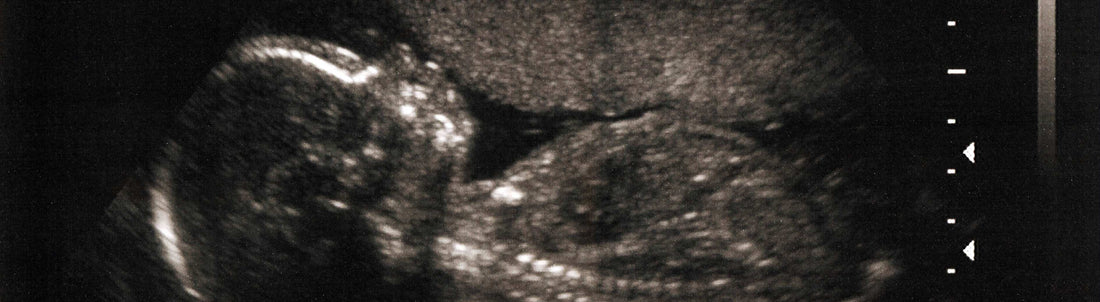

23 Weeks Pregnant: Baby's Senses Are Developing and You May Be Feeling More Tired

Congratulations! You've reached the 23rd week of your pregnancy. Your baby is growing and developing rapidly, and your body is going through some noticeable changes. Here are some common symptoms you might experience during this stage: